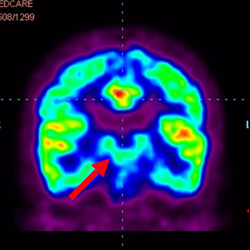

細胞治療前PET CT掃描顯示神經(jīng)組織中的藍/黑色區域,表明腦癱引起的大腦損傷。

腦癱細胞療法, 腦癱治療

細胞治療后,藍色和黑色區域減少,并且看到更活躍的區域。這表明損傷減少并改善了大腦功能。